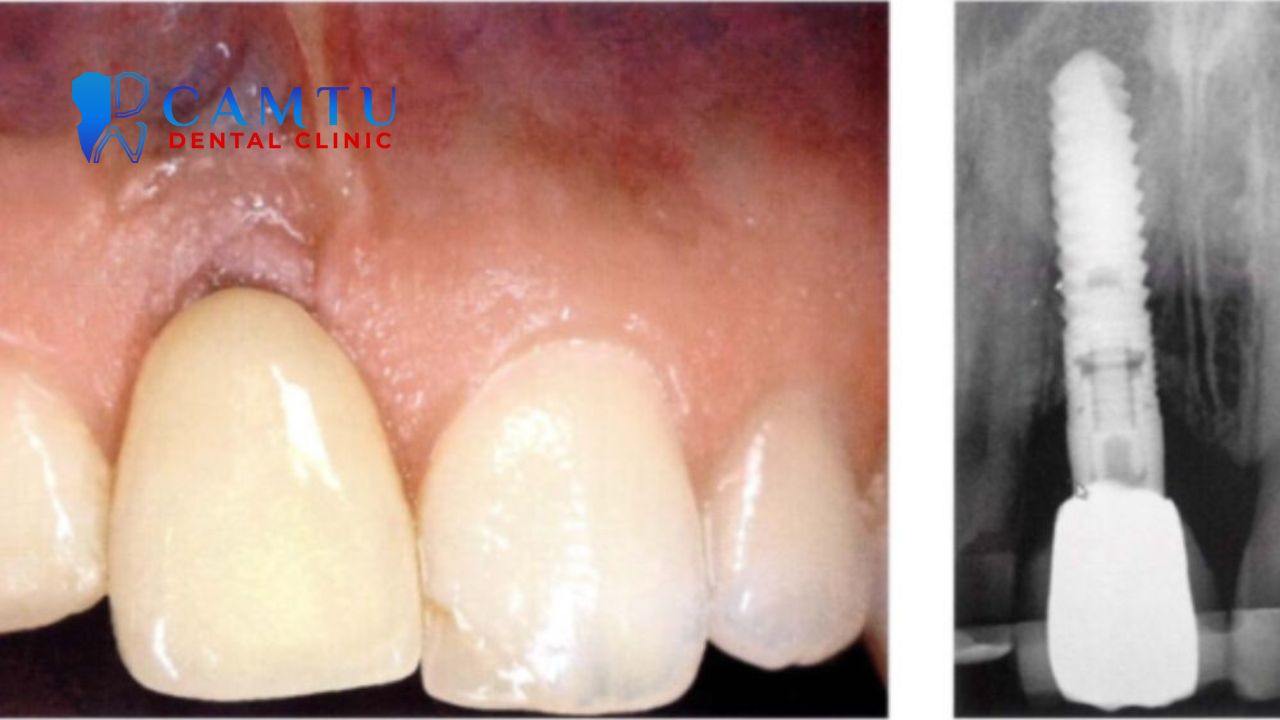

2. Tạo vùng mô dày quanh implant

Vùng mô mềm quanh implant nếu quá mỏng sẽ dễ viêm và kém thẩm mỹ. Ghép mô liên kết giúp tăng độ dày mô nướu, tạo hàng rào sinh học bảo vệ implant khỏi vi khuẩn. Điều này góp phần nâng cao tuổi thọ implant và hạn chế nguy cơ biến chứng lâu dài.

Ngoài yếu tố sức khỏe, cấy mô liên kết còn cải thiện đáng kể hình thể và màu sắc nướu quanh implant. Nhờ đó, phục hình trông tự nhiên hơn và hài hòa với các răng thật bên cạnh. Đặc biệt quan trọng ở vùng răng cửa, nơi yêu cầu thẩm mỹ rất cao.